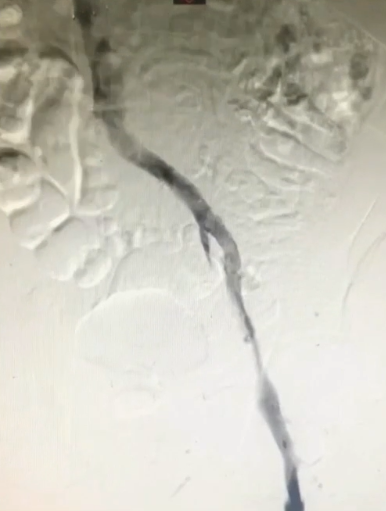

手术过程(五):复查造影见髂总静脉处仍狭窄,与家属沟通后,同意置入支架。引入髂静脉支架,定位准确后,谨慎释放,12 mm×40 mm球囊扩张髂静脉支架。

手术过程(六):造影见髂静脉血流通畅,支架形态满意,血流速度可,侧支循环消失。遂拔除鞘管,加压包扎,手术完成。